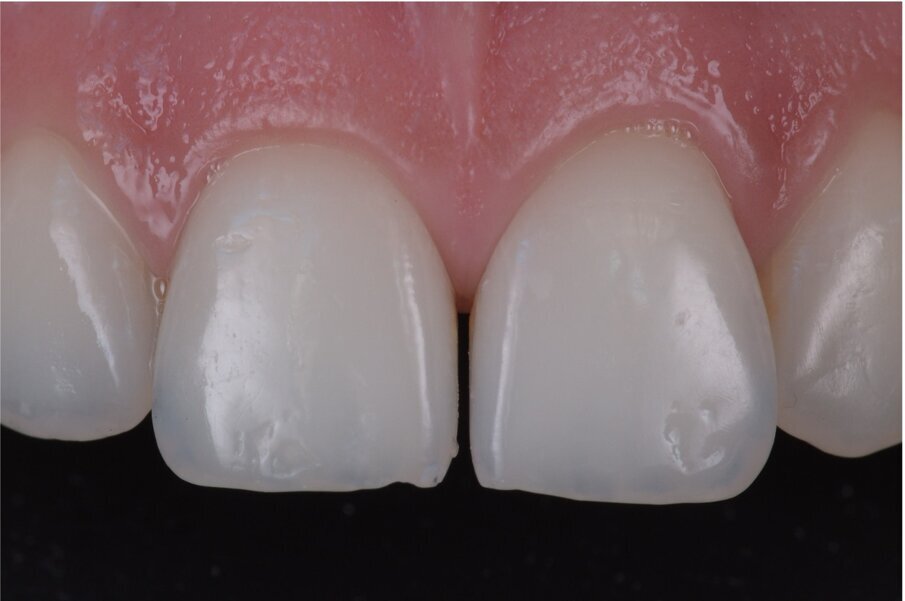

Fig. 5: Perfect emergency profile with front-wing technique. Courtesy of Dr. Jun Iwata, Japan.

You generate RETRACTION with the rubber dam on the most critical area which corresponds to the zenith and emergence profile, impossible to do with any kind of wax-up (Fig. 5).